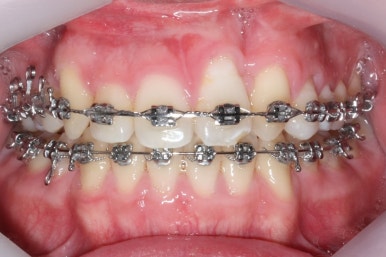

악궁확장과 동반하여 부산구순구개열 키다리아저씨치과에서는 브라켓을 부착하여 가지런하게 하는 작업을 시작하였습니다.

위아랫니가 각각 가지런해지고 있는 것을 볼 수 있습니다.

윗니는 아직 가지런하게 하는 작업 중이며, 아랫니는 가지런하게 하는 작업은 거의 다 되었습니다.

계속 윗니는 가지런히 해주고 있으며 아랫니는 앞뒤를 뒤로 당기고 있습니다.

거꾸로 물리던 앞니가 서서히 개선되어 가는 것을 볼 수 있습니다.

부산구순구개열 키다리아저씨치과에서 교정치료 하신지 1년여만에 드디어 앞니는 거꾸로 넘어왔고, 윗니들도 상당히 많이 가지런해졌습니다.

이 뽑은 자리도 상당히 많이 줄어든 것을 볼 수 있고, 이제는 정상적인 포개짐이 만들어졌습니다.